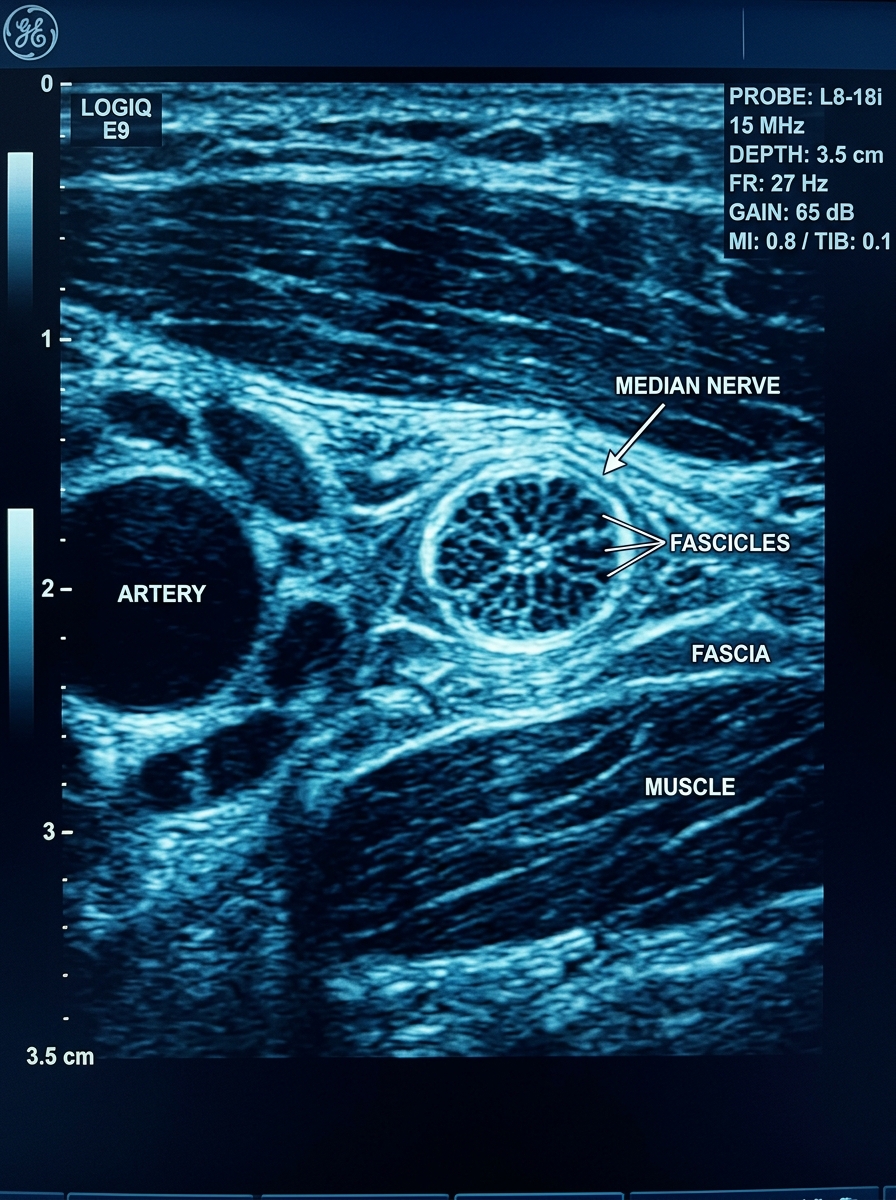

O Ultrassom Muda o Jogo

Ultrasound Nerve Cross Section

Visualização em Tempo Real

Permite identificar variações anatômicas individuais antes da injeção

Redução de Falhas

Metanálises mostram redução de 30–40% nas falhas de bloqueio com guia ultrassonográfica

Segurança Aumentada

Menor risco de punção vascular e lesão nervosa direta

Recomendação atual: ultrassom como padrão-ouro para bloqueios de plexo e nervos periféricos — Sociedade Europeia de Anestesia Regional (ESRA)

Recomendação atual:

ultrassom como padrão-ouro para bloqueios de plexo e nervos periféricos — Sociedade Europeia de Anestesia Regional (ESRA)